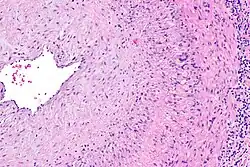

The gold standard for diagnosing temporal arteritis is biopsy, which involves removing a small part of the vessel under local anesthesia and examining it microscopically for giant cells infiltrating the tissue.[23] However, a negative result does not definitively rule out the diagnosis; since the blood vessels are involved in a patchy pattern, there may be unaffected areas on the vessel and the biopsy might have been taken from these parts. Unilateral biopsy of a 1.5–3 cm length is 85-90% sensitive (1 cm is the minimum).[24] Characterised as intimal hyperplasia and medial granulomatous inflammation with elastic lamina fragmentation with a CD4+ predominant T cell infiltrate, currently biopsy is only considered confirmatory for the clinical diagnosis, or one of the diagnostic criteria.[11]